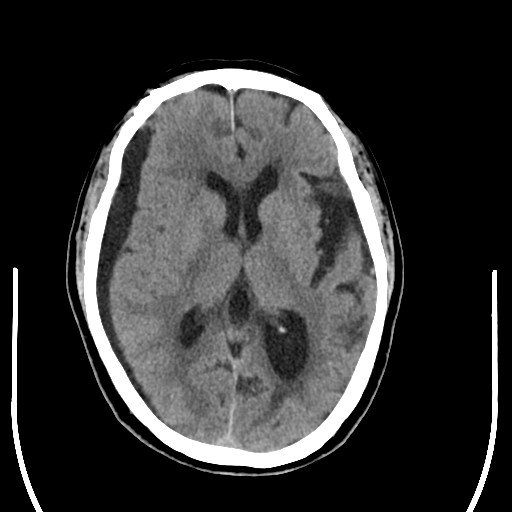

出院后2个月,患者出现"头痛,左侧下肢无力",头部ct提示硬膜下积液出院

图片尺寸512x512